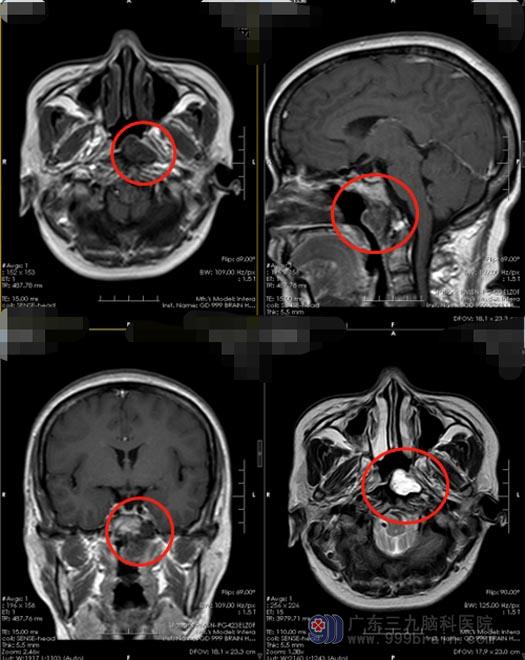

39岁的小刘,1年前因鼻腔肿物在当地医院就诊,头颅检查提示“斜坡占位性病变,考虑脊索瘤可能”,行肿物切除术,术后病理检查结果:脊索瘤。

2个月前,小刘出现左侧耳鸣,嗡嗡地响,当地医院头颅MR提示肿瘤复发。

这一次,小刘一家人选择去广东三九脑科医院进行治疗。11月2日入住神经外五科,头颅MR明确显示:斜坡脊索瘤切除术后复发可能。鲁明主任带领团队决定为患者经鼻在内镜直视下行复发肿瘤切除术。

▲术前